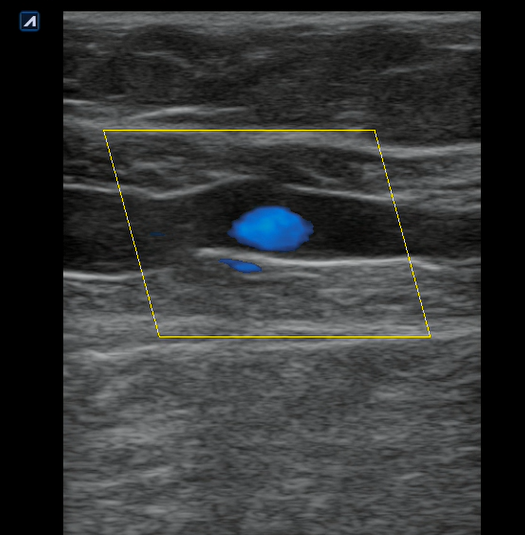

Se realiza ecografía clínica en consulta donde observamos a nivel inguinal adecuada compresibilidad de vena femoral y relleno con Doppler color. Cayado de safena libre y compresible. A 7 cm de distancia del cayado se aprecia, en territorio de safena, dilatación no compresible de la misma, contenido intraluminal ligeramente ecogénico y ausencia de Doppler color compatible con trombosis venosa superficial de 19 cm de distancia. Se estudia recorrido donde se observa en zona de dilataciones varicosas material ecogénico con ausencia de paso de Doppler alternando con zonas de paso parcial. En tercio distal de muslo comienza a desaparecer. Vena femoral profunda, poplítea y perforantes sin datos de trombosis.